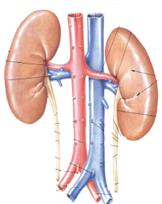

ФІЗІОЛОГІЯ СЕЧОВИДІЛЬНОЇ СИСТЕМИ

Відділи нефрону:

- капсула Шумлянського – Боумена;

- звитий канадець І порядку \ проксимальний\;

- петля Генле;

- звитий канадець ІІ порядку \дистальний\.

Процес сечоутворення:

- Фільтрація – утворюється первинна сеча; 180 – 200л за добу.

- Реабсорбція – повторне всмоктування в кров; \вторинна або кінцева сеча, 1 -1,5 л за добу\

- Секреція.

Склад первинної сечі:

Відповідає складу плазми за виключенням білків та еритроцитів.

Показники вторинної сечі:

Кількість – 1 -1,5 л

Колір – світло – жовтий

Забезпечується барвниками: уробілін, урохром.

Ракція сечі – слабо кисла – 4,5 – 8,0

Залежить від харчування:

- змішана їжа – слабо кисла;

- білкова - реакція кисла;

- рослинна – нейтральна або лужна.

Відносна щільність сечі 1,015 – 1,025

Залежить від прийнятої кількості рідини.

ФІЗІОЛОГІЯ СЕЧОВИДІЛЬНОЇ СИСТЕМИ

Склад сечі:

- Азотисті продукти розпаду білка:

сечовина, сечова кислота, аміак, пуринові основи, креатинін, індикан.

- Небілкові похідні:

солі щавелевої кислоти, молочна кислота, кетонові тіла.

- Неорганічні солі:

хлорид калію, натрію, сульфати, фосфати.

При патології в сечі можуть з’явитися:

- еритроцити - гематурія – при патології на рівні капсули.

- глюкоза – глюкозурія – цукровий діабет,

- лейкоцитів \ до 8 в полі зору\ - лейкоцитурія – запальний процес в сечовидільній системі.

- білки –протеїнурія – при патології на рівні капсули.

Регуляція сечоутворення:

А. Нервова регуляція сечоутворення:

Симпатична нервова система – звужує судини – знижує фільтрацію.

Парасимпатична нервова система – збільшує утворення первинної сечі.

Б. Гуморальна регуляція сечоутворення:

Вазопресин \ антидіуретичний гормон задньої долі гіпофізу\ - сприяє реабсорбції води.

Альдостерон - \ гормон кори наднирникових залоз\ - забезпечує реабсорбцію натрію та екскрецію калію.

Натрійуретичний гормон \ гормон передсердя\ - забезпечує реабсорбцію натрію.

Кальцитонін \ гормон щитоподібної залози\ - знижує реабсорбцію кальцію.

Паратгормон \ гормон при щитоподібної залози\ - підвищує реабсорбцію кальцію.